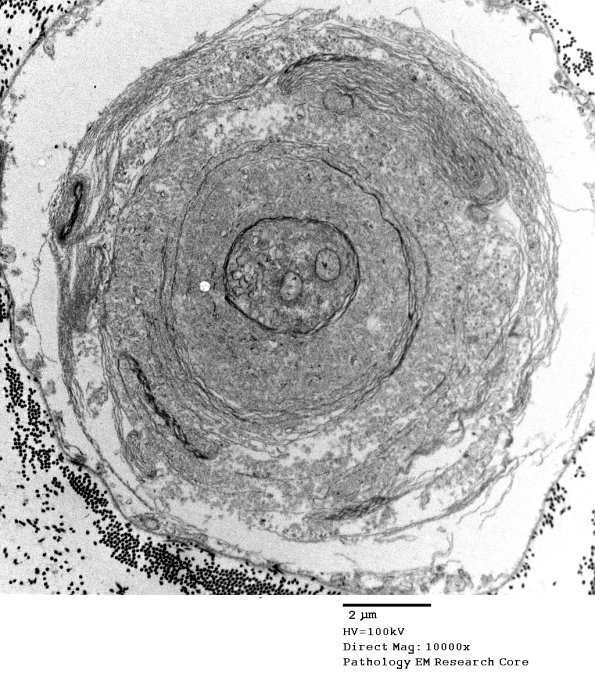

19E2 Artifact, myelin EM 020 - Copy

The pattern varies from axon to axon in the same nerve. (electron micrograph)